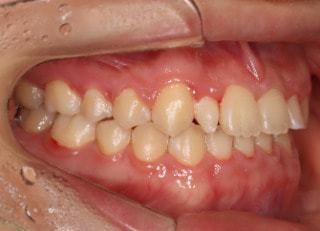

症例紹介

上顎2番矮小歯右下2番先天欠如

治療法:フルパッシブブラケット:T21

解説:下顎前突上顎劣勢長傾向で、上顎両側2番が矮小歯、右下2番先天欠如症例なので、上下前歯の幅径の比率を調節する必要があるケースです。(ご本人のご都合で治療中に来院できない期間がありました)

治療前